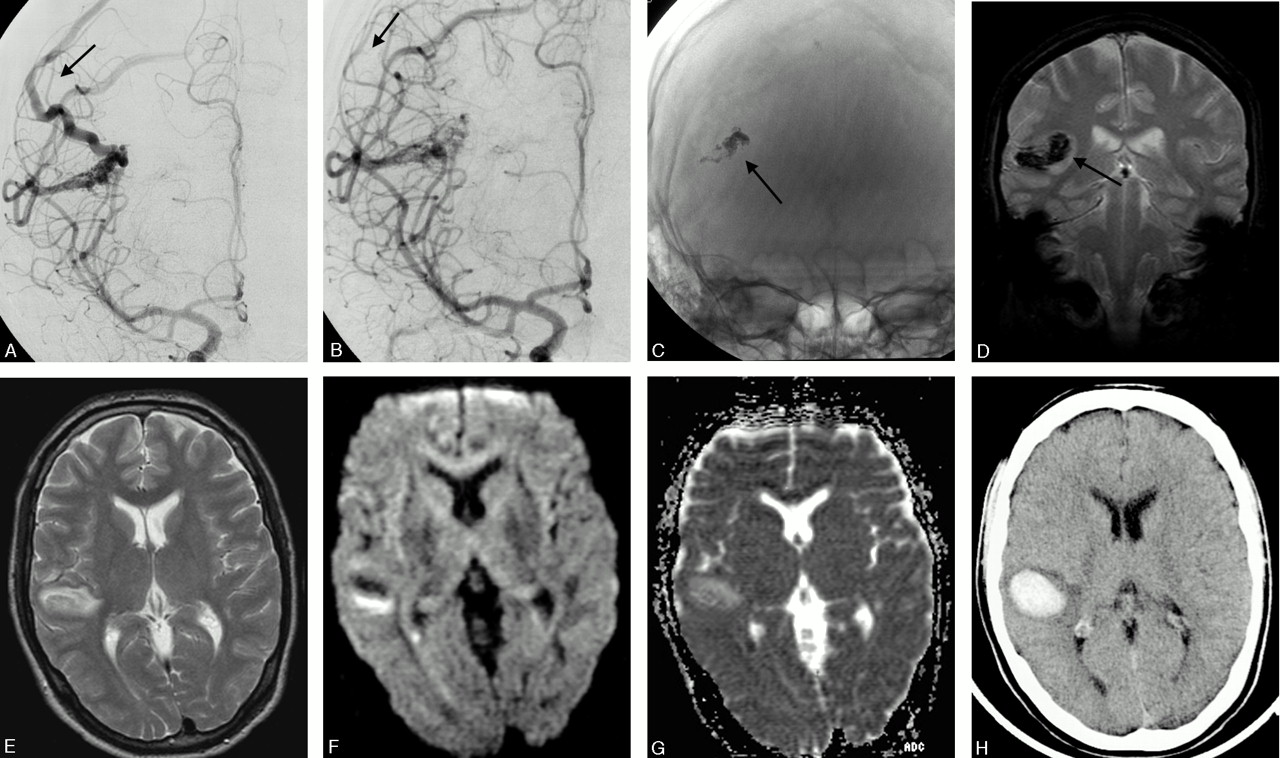

Patient with a small temporal AVM.

A and B, Frontal projections of internal carotid angiogram done before and after an uneventful embolization. One of 2 draining veins is patent after the treatment.

C and D, Illustrate the cast of glue on unsubtracted DSA and on coronal MR (2D FLASH, performed 26 hours after treatment). The susceptibility artifacts caused by the glue are well illustrated but an associated hematoma could not be definitely defined.

E–G, Axial MR (T2-weighted, DWI b 1000, and ADC maps) performed after treatment show a vasogenic edema in the surroundings of the AVM nidus (arrowhead).

H, Axial CT, performed 2 days later in conjunction with sudden onset of minor symptoms, shows a small hematoma in the area of previous edema. The AVM showed a complete and spontaneous occlusion at follow-up.

Vasogenic edema surrounding a draining vein was found in one patient before treatment and resolved after embolizations and shunt reduction. Although the procedures were uneventful, vasogenic edema appeared around the nidus on MR imaging immediately after treatment in 4 patients and between treatments in one patient with a progressive venous occlusion (Fig 5). Perfusion was decreased in the area of edema. The edema was initially asymptomatic in the first 4 patients. Three days later, 2 patients developed paresthesia and hemiparesis, respectively, both transient. In one of the patients, however, allodynia developed later. In each of the 2 patients, postprocedural MR imaging, including FLASH images, failed to visualize a hemorrhagic component, though a minor hematoma organized around the AVM nidus was revealed on CT performed 2 days later (Fig 3). However, the virtually identical appearances of the susceptibility artifacts generated by glue and hemorrhage may explain the failure of FLASH sequences to identify the hemorrhage.

Early asymptomatic hematomas showing typical patterns on MR imaging, including DWI, were seen in 2 patients subsequent to uneventful procedures.55,56 The bleeding may have been caused by a vascular tear associated with the retraction of the catheter or by overextension of the nidus/vessel during embolization.